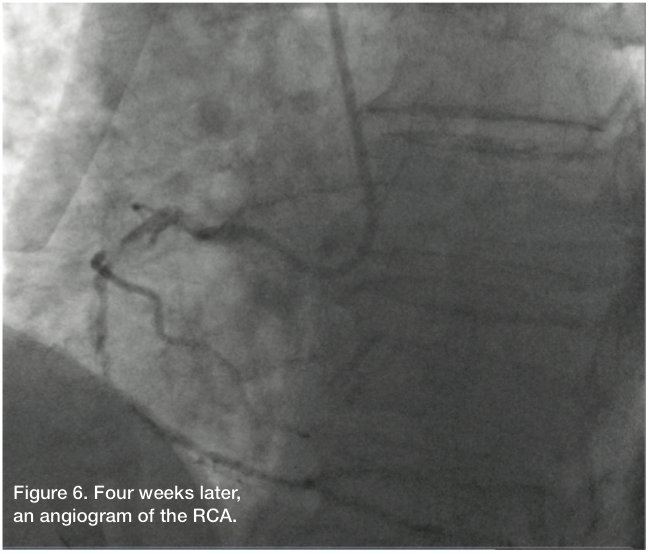

Four weeks later, the patient presented for elective revascularization of the RCA. The right radial artery was prepped and draped in sterile fashion. The right radial artery was accessed with a 6 Fr Glidesheath using Doppler guidance, as the pulse was not very palpable. The left radial artery was accessed with a 6 Fr Glidesheath in anticipation of doing dual injections.

Angiographic findings

The RCA had a proximal 99% stenosis with an obvious dissection. The remaining proximal to distal RCA was diffusely diseased, 70 to 80%. We used a 6 Fr AL 0.75 guide with side holes.

The patient’s angiographic finding demonstrated a degree of patency, a result of the previous retrograde balloon dilation of the RCA. We changed to an Amplatz right (AR) Mod guide catheter, because the AL 0.75 was engaging the dissection too deeply and would not allow us to steer our wire in the desired direction. Using a Fielder wire and a 1.25 mm balloon, we were able to cross, and advance the balloon and wire distally into the PDA and exchange out for an Iron Man support wire (Abbott Vascular). After removal of the 1.25 balloon (Medtronic), we predilated with a 2.0 x 15 Apex catheter (Boston Scientific). This was then followed by a 2.5 x 15mm AngioSculpt (Angioscore) to predilate the mid and distal RCA. Intravascular ultrasound (IVUS) (Volcano) showed that the vessel was actually about 3.0 mm in the distal and mid portion, with a dissection clearly noted in the proximal portion. The vessel was about 4.0 mm proximally. We took a 3.0 x 30 mm Resolute (Medtronic) drug-eluting stent and deployed it from the distal to mid RCA. The Resolute was overlapped with another 3.0 x 30 mm Resolute, and then a 3.5 x 26 mm Resolute, going all the way back to the proximal RCA, but not involving the ostium. All stents were post dilated with Quantum balloons at high pressure. Stent size and apposition was confirmed by IVUS. Final angiography revealed TIMI-3 flow without dissection, perforation, or embolization. The patient had an uncomplicated hospital course and was discharged home the next morning.